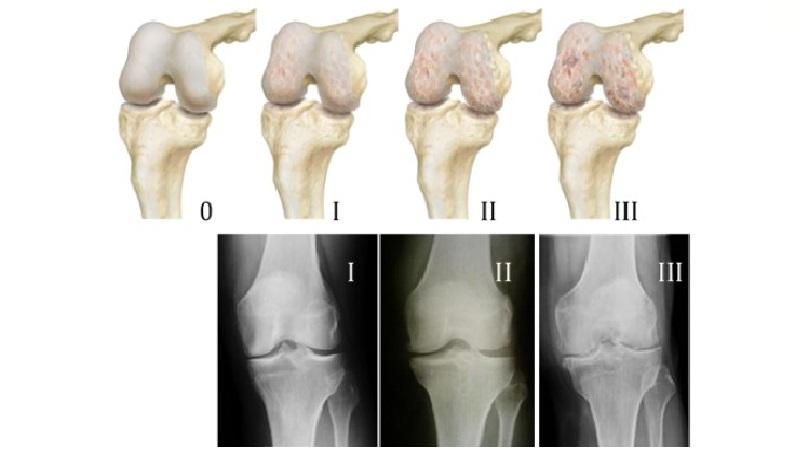

Симптомы и стадии заболевания

На протяжении многих лет болезнь может развиваться, и первые признаки артроза зачастую бывают едва заметны – это может быть боль в колене, возникающая при физической активности, утреннее чувство тяжести в ногах и скованность.

На более поздних стадиях артроза (вторая стадия) симптомы становятся более выраженными – при движении в суставе слышен хруст и треск, которые сопровождаются болевыми ощущениями. В суставной сумке может накапливаться жидкость (выпот), функциональность коленного сустава значительно снижается, а деформация становится заметной невооруженным глазом.

Третья стадия заболевания характеризуется сильным или полным разрушением хрящевой ткани, ограничением подвижности и постоянной болью, даже в состоянии покоя. Изменение походки становится очевидным из-за деформации коленных суставов, также может наблюдаться метеозависимость.

Четвертая стадия представляет собой полностью деформированный и нефункционирующий коленный сустав, при котором суставная щель отсутствует, хрящ разрушен, а кровеносные сосуды испытывают сжатие. В этом состоянии колено теряет способность сгибаться и разгибаться, что приводит к утрате трудоспособности.